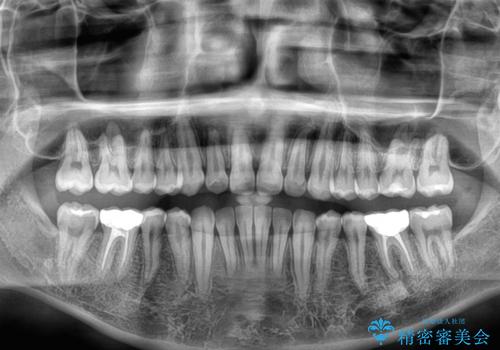

- 前歯のデコボコを気にして来院された患者様です。

矯正治療後は、奥歯の銀歯をセラミッククラウンにて補綴治療を行うこととしました。

あっという間に歯列が整い、目立っていた銀歯もなくなり、清潔感のある口元になりました。